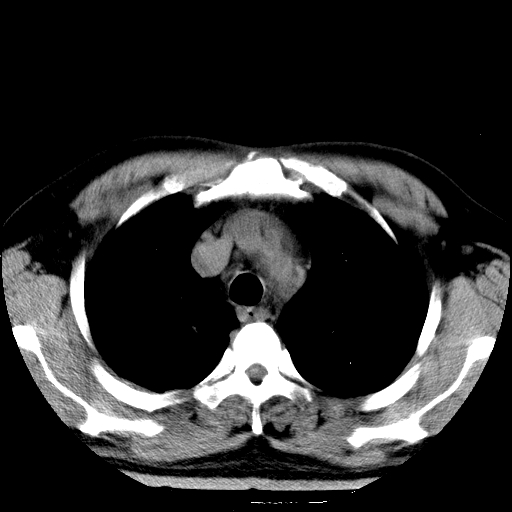

标题: CT21804:男,65岁,咳嗽、咳痰、发热5天。 [打印本页]

男,65岁,咳嗽、咳痰、发热5天。

慢支 肺间质纤维化合并感染!

支气管扩张合并感染,胸膜肥厚

考虑慢支并感染,肺间质纤维化。

两肺间质性炎症并感染

慢支,肺心病

支持慢性支气管炎伴感染,双侧少量胸腔积液.

两肺间质纤维化,支扩合并感染,双侧胸腔积液

感染,肺间质纤维化。

慢支 肺间质纤维化合并感染

支持慢性支气管、肺间质纤维化合并感染。

慢性支气管炎并感染,支扩,双侧少量胸腔积液.